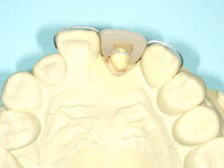

矯正による歯牙の挺出をエクストリュージョンといい、歯に持続的な力を加えることにより、健全歯質(虫歯に侵されていないところまで)を引っ張り出す方法(部分矯正)です。

歯茎の線に左右差がないので、外科的に埋まっている根っこ(歯根)を出してしまうと審美的問題が起きてしまいます。

外科的に被せ物を作るときに必要な健全歯質を作り出すことです。

被せ物のために、必要とされる部分の歯を意図的に作り出す治療法になります。

根っこ(歯根)が歯茎の中にあり、このままでは差し歯に出来ない状態です。

歯茎を隣の歯と合わせ審美的な点からも治療し、差し歯に出来るようにしました。